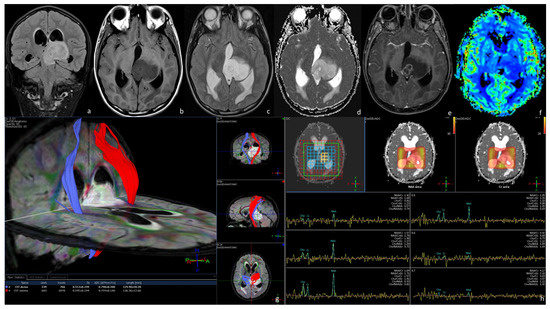

3.1. Diffuse Intrinsic Low-Grade Gliomas (DILGGs)

3.2. Enhancing Malignant Gliomas (EMGs)